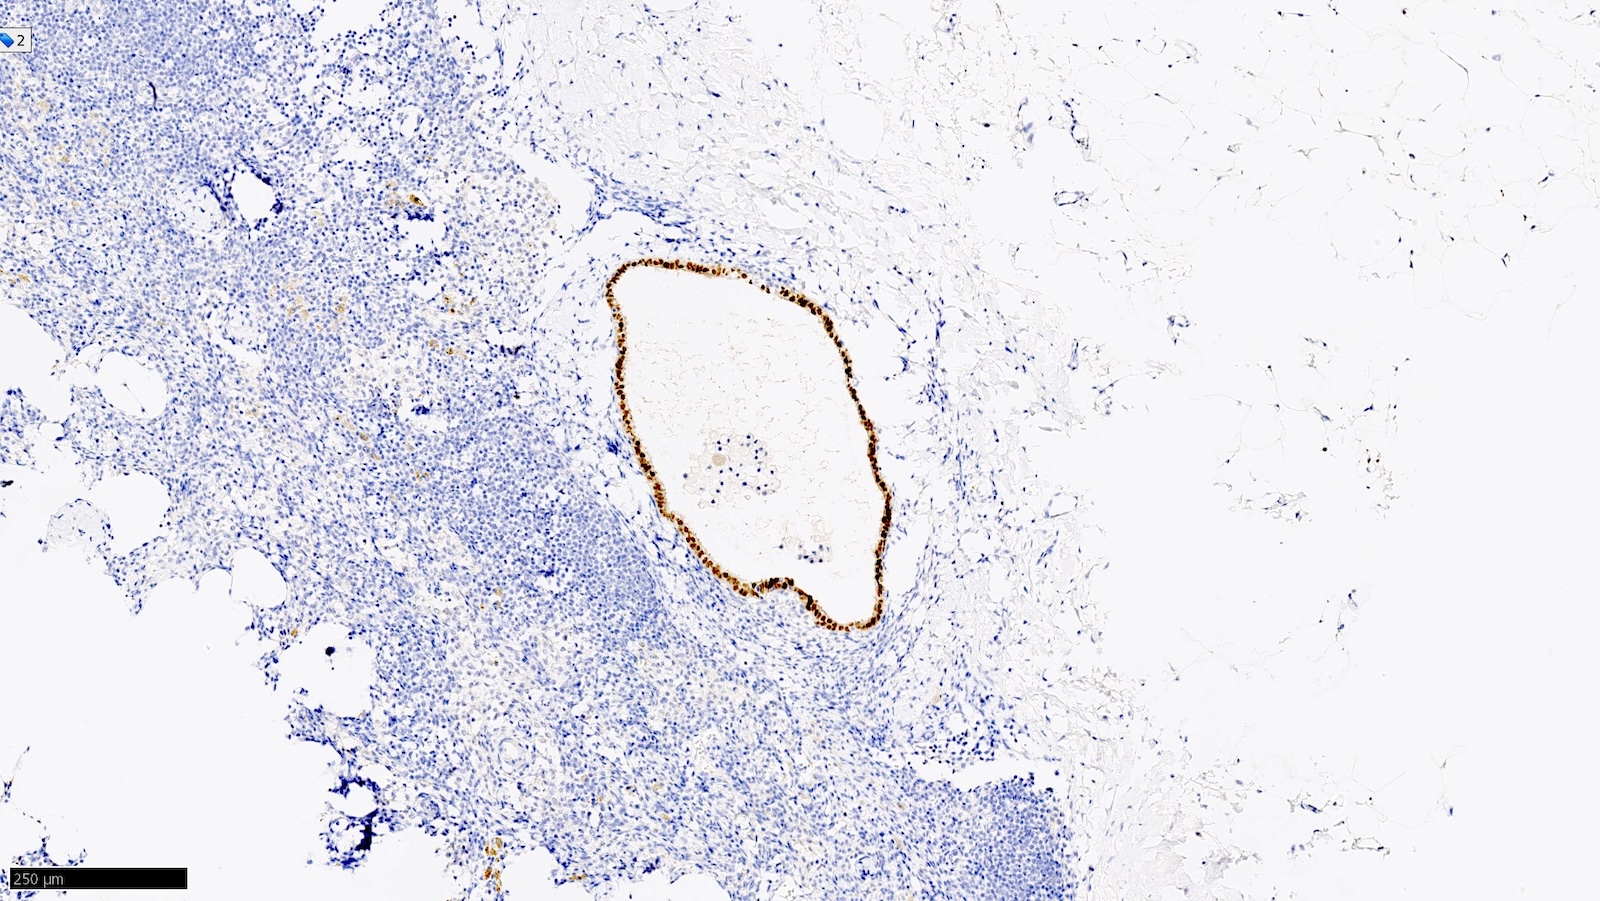

Microscopic (histologic) images

Contributed by Sucheta Srivastava, M.D., Jaya Ruth Asirvatham, M.B.B.S., Rahul Koshy, D.O. and Julie M. Jorns, M.D. (Case #548)

Positive stains

- Note: "enhanced methods" of SLN metastasis detection, including routine immunohistochemistry, are not recommended (i.e. should be used on a case by case basis / when necessary for diagnosis) (J Clin Oncol 2014;32:1365)

- AE1 / AE3, CK7, GATA3

- Estrogen receptor / ER (depends on biomarker status)

- Reference: Semin Diagn Pathol 2018;35:143

- Benign epithelial inclusions in axillary lymph node (Int J Surg Pathol 2018;26:564, Breast J 2020;26:274):

- These inclusions can be glandular (most common) or squamous epithelium lining cystic lumina

- Glandular inclusions often have a luminal and myoepithelial cell layer

- Immunoreactivity for myoepithelial cell markers (p63, calponin, SMMHC / smooth muscle myosin heavy chain, actin - alpha smooth muscle) is often demonstrable but it may be variable or absent in morphologically benign inclusions

- Endosalpingiosis of axillary lymph nodes (Case Rep Pathol 2016;2016:2856358, Am J Surg Pathol 2010;34:1211, Breast J 2020;26:274):

- Müllerian type glandular inclusions lined by cytologically bland cuboid to columnar epithelial cells that are reminiscent of fallopian tube type lining or coelomic type lining

- Cilia, when present, is a reassuring feature to confirm a benign diagnosis

- Positive for PAX8 and WT1 (good markers of Müllerian origin) and negative for GATA3